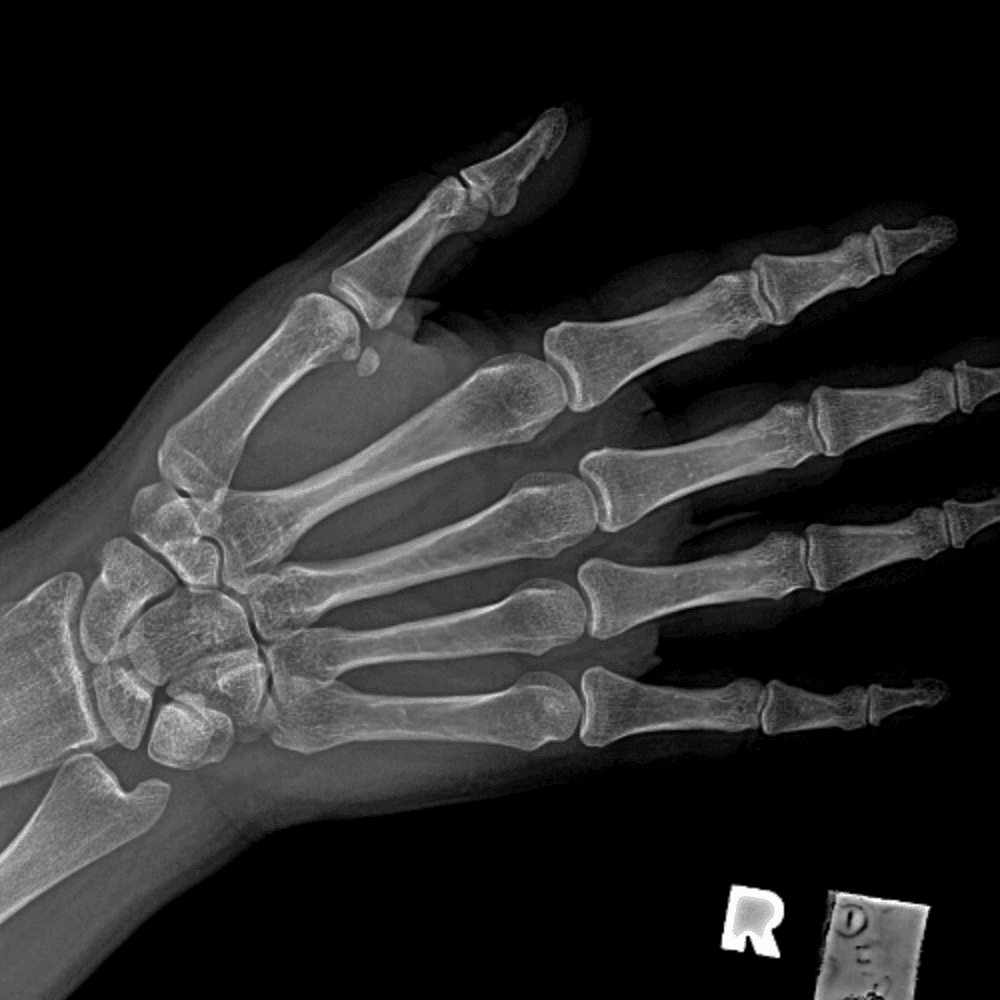

Simuliert den Dienst durch subtile oder schwierige Fälle und einige Normalbefunde.

30 Fälle